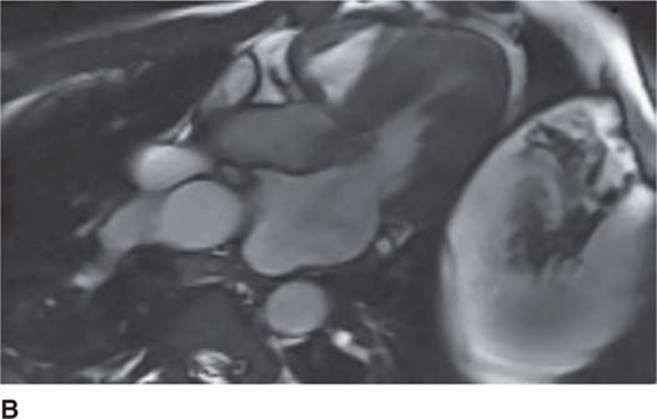

The 12-lead ECG (see Figure 53-1) should demonstrate LVH and repolarization abnormalities. Incongruence between the ECG and echo findings should lead to definitive evaluation with either cardiac magnetic resonance imaging (CMRI)(Figure 53-7A and 53-7B) or invasive hemodynamic studies in the cath lab. In order to help assess the risk of SCD, HCM patients should also have 24-hour Holter monitoring and a graded exercise test performed at the time of diagnosis to evaluate for the presence of asymptomatic arrhythmias and determine the blood pressure response during exercise.1,4

FIGURE 53-7A Cardiac MR with open mitral inflow during diastole. (Used with permission of Dr. Andrew Rivard at University of Mississippi Medical Center, Jackson, MS.)

FIGURE 53-7B Cardiac MR with obstruction of the LVOT during systole due to SAM of the mitral valve. (Used with permission of Dr. Andrew Rivard at University of Mississippi Medical Center, Jackson, MS.)